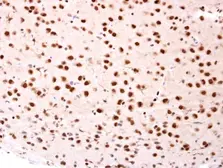

Description Rabbit PolyclonalApplications WB ICC/IF IHC-P IPReactivity Hu, Ms, Rat, Zfsh, Rb, Dm, Bov, Dog, Hm, Chk, Pig, Mk, C. elegans, E. coli, Mosq, Nematode, Pika, Plant, Fish, Bacteria, Insect, milkfish$419100μl$16925μl -

Description Rabbit PolyclonalApplications WB IHC-P IHC-FrReactivity Hu, Ms, RatSummary This antibody was raised against human NSE (ENO2) protein, but it may cross react other family members based on sequence homology.